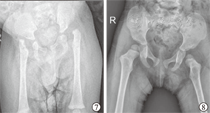

本组8例中,男5例,女3例;初次手术年龄5~39个月,平均16个月。8例合并有双侧先天性马蹄内翻足(congenital clubfoot, CCF),占100%;1例合并双侧先天性垂直距骨(congenital vertical talus, CVT),占12.5%;4例合并单侧膝关节畸形(3例膝关节脱位、1例膝关节过伸),占25%;2例合并双侧腕关节屈曲挛缩畸形,占25%。病例纳入标准符合以下条件:①初次诊断和治疗均在我院,并获得连续随访者;②X线片诊断为双侧髋关节脱位;③出生时至少身体2个不同部位有关节挛缩畸形;④排除进行性神经疾病及其他畸形髋关节脱位者;⑤关节两端变细伴广泛肌肉失用性萎缩;⑥正常关节皮肤皱褶消失(图1、图2)。

所有病例均获随访,随访时间2~5.2年,平均3.5年,其中2例步态基本正常,1例轻微跛行,2例步态不稳,1例需佩戴长腿支具行走,2例不能独立行走。4个髋关节活动基本正常,8个髋关节活动轻度受限,4个髋关节活动明显受限。根据Severin X线片评定标准和修改的McKay临床评定标准,优4髋,良8髋,中4髋,优良率为75%(图3,图4,图5,图6)。

AMC髋关节双侧脱位患儿应尽早进行手术治疗。Wada等[15]建议髋关节的切开复位时间应该等到10~18月龄,因为其治疗的大部分病例联合股骨和骨盆截骨术,而足、膝、髋畸形的矫正应在患儿3~10月龄同时进行,这样可以减少制动时间,降低关节僵硬的风险,使患儿更好适应社会。Stilli等[13]认为治疗的最佳年龄应在8~10月龄,足膝的畸形矫正时间分别为3~4月龄和6~7月龄,这样逐步矫正不会导致手术过程的复杂性。Szöke等[7]建议患儿在3~6月龄时行切开复位同时矫正足膝的关节挛缩,而年长患儿应行一期骨盆截骨及股骨短缩旋转截骨是更好的治疗选择。本组4例<12月龄患儿行了单纯前路切开复位手术,其中2例在5月龄行切开复位者,术后随访中4个髋关节活动基本正常(图7、图8),相比2例12月龄患儿,其髋关节活动范围显著增大、活动范围评分明显高,同时手术操作过程简单。因此,AMC髋关节双侧脱位患儿一经诊断,应早期选择手术切开复位,年龄越小手术过程也相对简单、术后髋关节临床效果越满意,此期间需同时进行其他部位畸形的矫正。